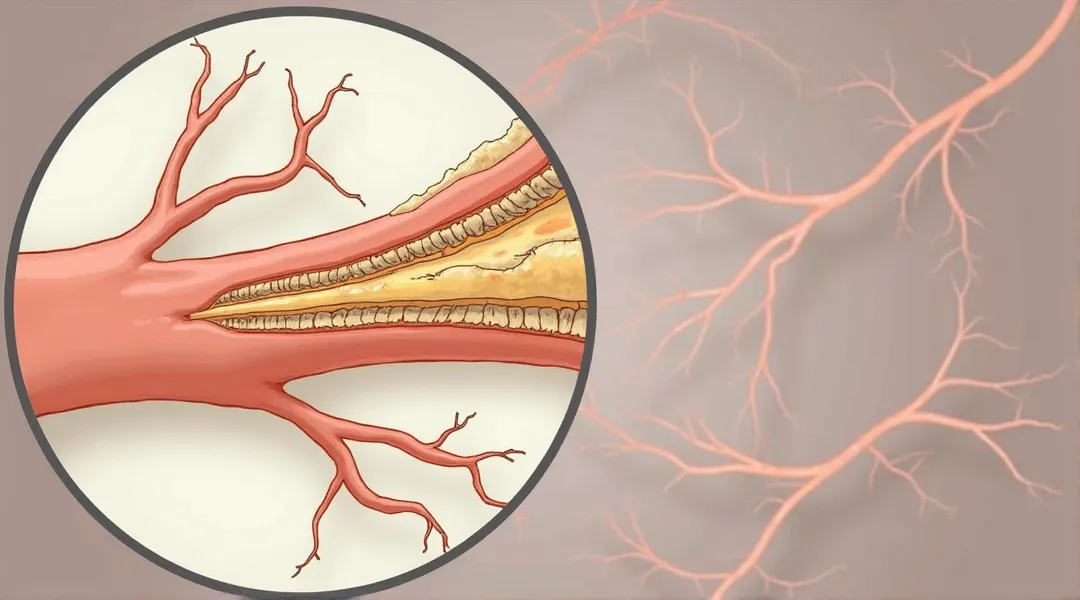

Epidermis Fermis Hypodermis Keratinized squamous stratified epithelium Hair Sebaceous gland Sweat gland Pilo erector muscle Connective tissue Blood vessels Nerves Adipocytes